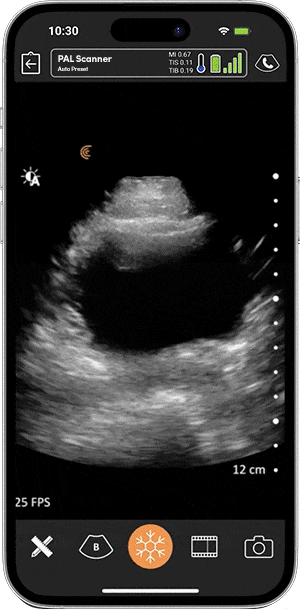

Una parte integral de la medicina de emergencia, el ultrasonido en el punto de atención se reconoce como «una habilidad importante que influye positivamente en los resultados del paciente«. Al personal de emergencia les encanta la alta portabilidad, la facilidad de uso y la calidad de imagen superior del escáner multipropósito Clarius C3 HD3 para imágenes de cuerpo completo. Al acelerar la clasificación y el tratamiento, los médicos están salvando vidas con Clarius en la mano.

Inalámbrico y basado en aplicaciones, Clarius ofrece imágenes rápidas y detalles nítidos al lado de la cama. Obtenga imágenes de alta definición y el rendimiento de los sistemas de ultrasonido tradicionales en un escáner ultra móvil muy asequible que se empareja instantáneamente con sus dispositivos iOS o Android.

Valoración Focal del paciente Politraumatizado mediante Ecografía (eFAST por sus siglas en inglés) puede identificar sangrado o líquido libre en múltiples compartimentos anatómicos. EL auto ajuste con IA de Clarius les permite el cambio instantáneo a manos libres para optimizar el escaneo de cada sistema de órganos. Se ha demostrado que eFAST identifica rápidamente lesiones críticas en pacientes con trauma abdominal, especialmente importante para entornos con menos recursos.

El dolor o síncope abdominal o en el flanco vago puede ser la única presentación de un colapso cardiovascular inminente por una ruptura causada por un Aneurisma Aórtico Abdominal (AAA). El pre-ajuste abdominal de Clarius permite una visualización clara de la aorta abdominal con penetración adicional para aquellos con estructuras más profundas. El ultrasonido junto a la cama muestra un excelente rendimiento diagnóstico en el diagnóstico de AAA en pacientes sintomáticos.